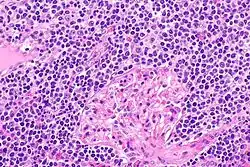

| EMZL infiltrating kidney tissue. | |

The histopathologic (i.e. microscopic) examination of EMZL lesions typically reveals a vaguely nodular or diffuse pattern of cells. The malignant cells in these lesions have, in varying proportions, the morphology of small-to-medium-sized lymphocytes, centrocyte-like B cells, centroblast-like B cells, monocyte-like B cells, plasma cell-like B cells, and/or large B cells. When the large B cells form prominent sheets that are clearly separated from cells with the other, low-grade malignant morphologies, the disease may be transforming to the far more aggressive malignancy, diffuse large B-cell lymphoma. This transformation occurs in ~18% of patients at a median of 4–5 years after the original diagnosis of EMZL.[22] Immunophenotyping or the neoplastic large B cells in these lesions shows that they express CD20 but not CD3 surface membrane B cell marker proteins. The cells almost always express BCL2 and may express MNDA (~70% of cases), CD23 (~33% of cases) and CD5 (~20% of cases) marker proteins but do not express the cyclin D1 marker protein.,[22] the T-cell marker, CD10, or BCL6.[1]